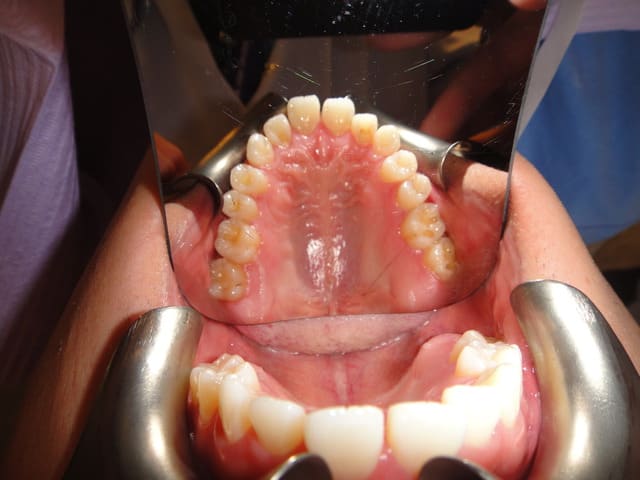

Patient asiatique, 25 ans, consulte car il veut corriger son crossbite bite antérieur localisé aux latérales et son crossbite secteur 2/3. Il aimerait également corriger son apparence générale, son profil notamment.

Classe III squelettique et dentaire.

il y'a une forte compensation alveolaire maxillaire superieure anterieurement et lateralement,

pour l'option chirurgicale je voudrais savoir pourquoi on a proposé l'extraction des 2 1eres premolaires vu quon a déja 2 dents manquantes au maxillaire superieur (3emes molaires),

je proposerai plutot un simple alignement et decompensation alveolo-dentaire sans extraction suivi de chirurgie orthognatique dexpansion maxillaire et de recul mandibulaire +/- avancée maxillaire (les deplacements des pieces osseuses dependent de notre diagnostic cephalometrique dans le sens sagittal)et extraction de 3emes molaires mandibulaires pour pouvoir coordonner les 2 arcades avec le meme nombre de dents.